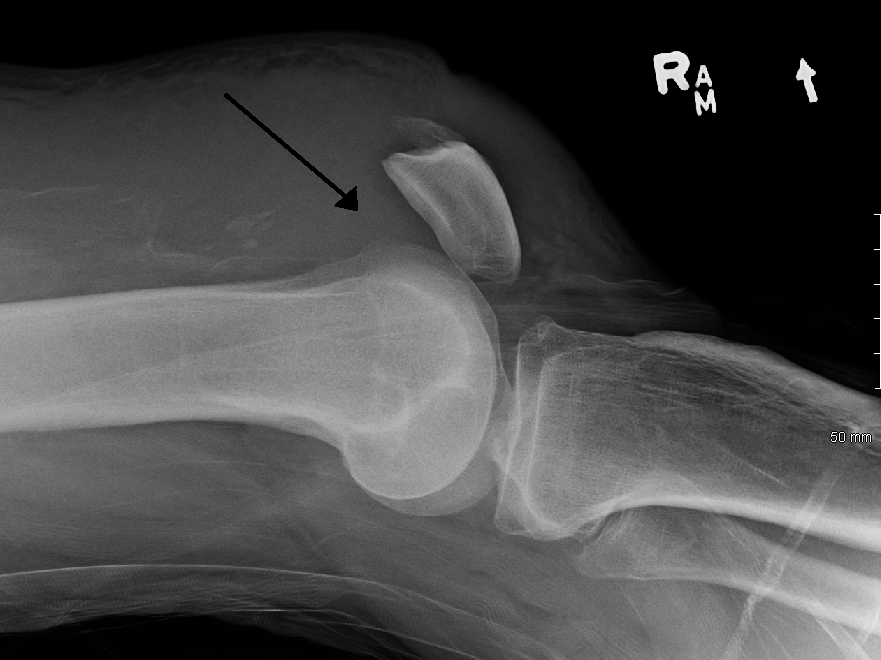

Patellar Instability and Dislocation